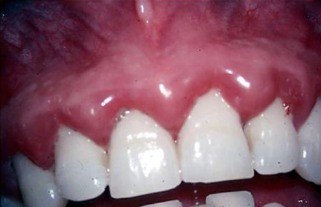

Case 1: Gingiva Bleeding